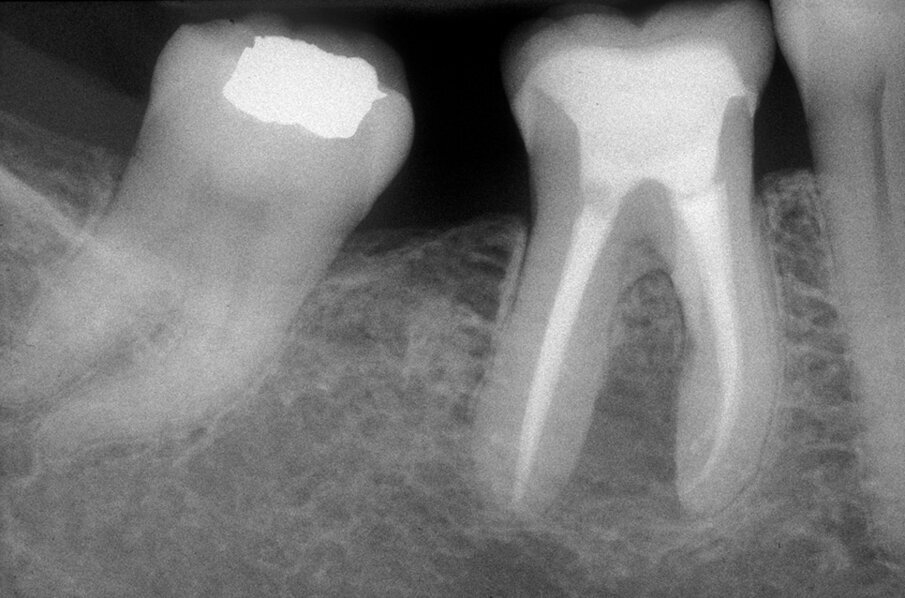

Queste perforazioni possono avvenire nel corso della strumentazione di canali curvi, per l’esecuzione del cosiddetto “trasporto esterno” del forame apicale. Una volta eseguita la perforazione, se l’operatore riesce a ritrovare e preparare il canale originale (con l’utilizzo di strumenti sottili e precurvati, molta irrigazione e soprattutto molta pazienza), il danno provocato dalla perforazione sarà minimo in quanto, soprattutto se la perforazione è piccola, si comporterà come un piccolo canale laterale che sarà facilmente otturato. Se invece il canale originale è rimasto intasato dai detriti di fango dentinale e gli strumenti ogni volta ripercorrono il cammino della perforazione, in tale caso il canale deve essere otturato con le metodiche tradizionali e successivamente l’apice contenente la porzione non trattata del canale radicolare deve essere rimosso per via chirurgica, soprattutto se stiamo trattando un dente necrotico o se siamo di fronte ad un ritrattamento (Figg. 1a-1e).

Le perforazioni del terzo medio avvengono nella maggior parte dei casi durante la preparazione della cavità d’accesso o, più spesso, durante le fasi di detersione e sagomatura o infine durante la preparazione dello spazio per un perno con l’utilizzo di frese tipo Largo, Peeso, Gates Glidden o simili (Figg. 2a-2f).

Tali perforazioni sono piuttosto frequenti a livello degli incisivi superiori, dove l’errore che più spesso viene commesso è rappresentato dall’utilizzo della fresa con eccessiva angolazione vestibolare. Perforazioni del terzo coronale possono anche accadere sul pavimento dei molari quando gli orifizi canalari vengono cercati in posti sbagliati. Tipiche sono le perforazioni nei molari superiori o inferiori, che avvengono per lo sfondamento del pavimento della camera pulpare (Figg. 3a-3i). Come conseguenza del trauma meccanico, si ha una rapida distruzione del legamento parodontale. L’osso alveolare immediatamente adiacente alla perforazione si riassorbe con conseguente perdita verticale di osso. Il processo infiammatorio quindi si estende coronalmente lungo le fibre del legamento parodontale, con distruzione del legamento, dell’osso alveolare e delle fibre gengivali sopracrestali. Come conseguenza di ciò, si ha la migrazione apicale dell’attacco epiteliale e le formazione di un grave difetto parodontale9.